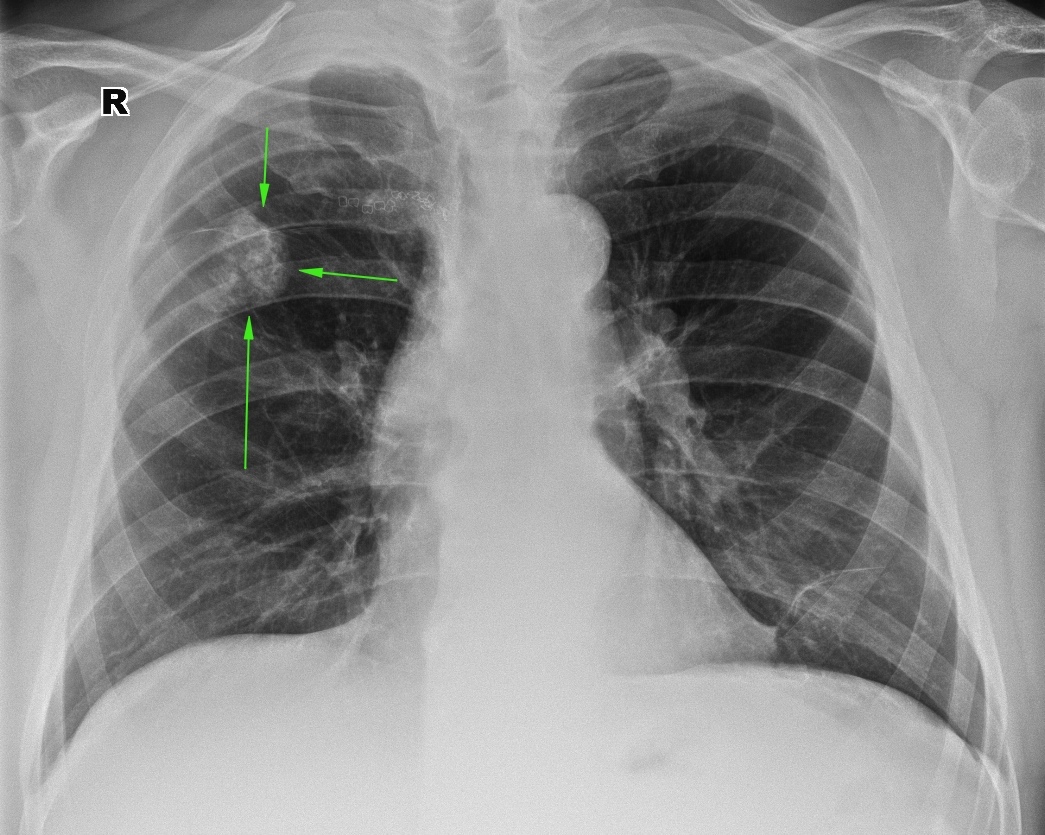

Симптомы и лечение инфильтративного туберкулеза легких

Раздел: Снимки-откровения